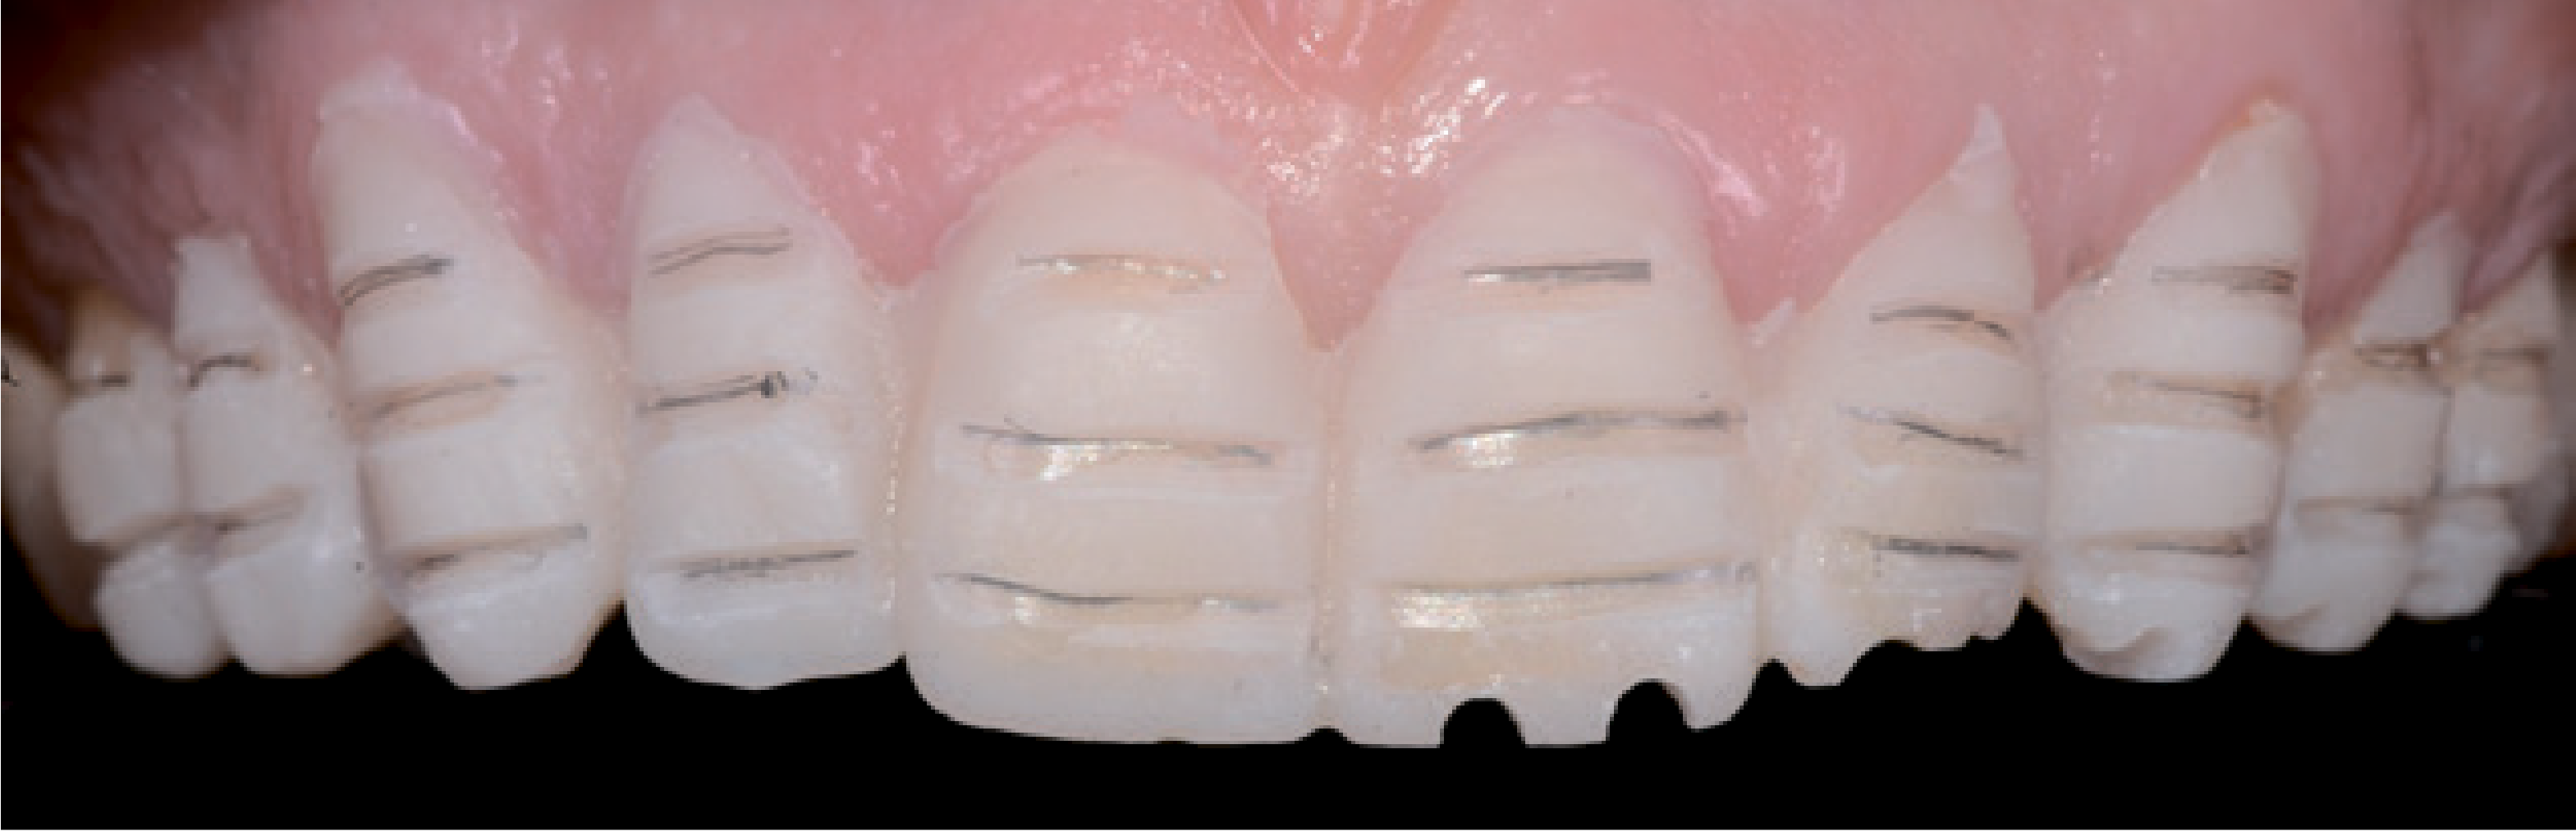

Згодом можна провести вибіркове препарування, приділяючи особливу увагу позначеним ділянкам, щоб суцільнокерамічні реставраційні конструкції були достатньо й рівномірно щільними, і щоб таким чином зубна дуга була рівною. Після такого прицільного видалення емалі конічним грубозернистим алмазним бором вестибулярні відпрепаровані ділянки простягалися рівномірно уздовж щічних поверхонь – від різального до ясенного краю, створивши гладкі скоси на емалі у зазначених зонах (мал. 12).

Відповідно, пришийкові кордони залишилися в емалі над поглибленнями. Тут основне завдання полягало в тому, щоб створити надійне з'єднання з емаллю. Шийкові відпрепаровані ділянки подовжили й вивели у міжзубні зони. Тут краям відпрепарованих ділянок надали невеликий скіс – на вестибулярному боці міжзубних точок контакту без ослаблення контакту проксимальної поверхні, щоб забезпечити стабільність і виключити будь-які зміщення. Поверхня відпрепарованих ділянок була згладжена полірувальним диском. Перед зняттям відбитка визначили відтінок зуба (мал. 13).